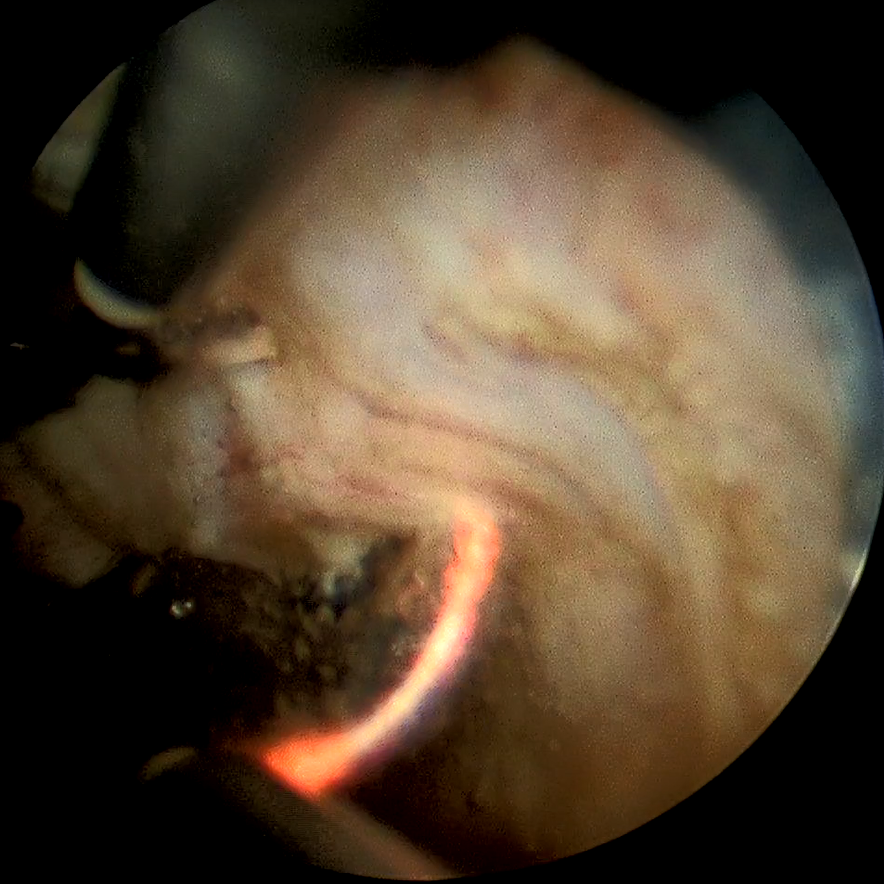

李新教授手术中仔细操作,在前列腺电切过程中仔细辨认输尿管开口,避免输尿管损伤,手术过程顺利,术中发现膀胱多发憩室,憩室可见数枚结石,术后诊断与术前诊断吻合,术后患者恢复良好。

经尿道前列腺电切手术(Transurethral Resection of the Prostate,简称 TURP)是目前治疗前列腺增生的金标准,也是一种微创手术的方法,使用一种特殊的器械也就是前列腺电切镜,进入尿道以后到达前列腺的位置,在电脑监视器的监视下观察前列腺增生的程度,对尿道压迫的程度,进一步观察尿道括约肌的位置,使用等离子或者使用电切的能量,将前列腺的组织分割切除,将体积较大的前列腺分割成小块,再由尿道运出体外,所以不需要开刀就可以进行前列腺的切除。